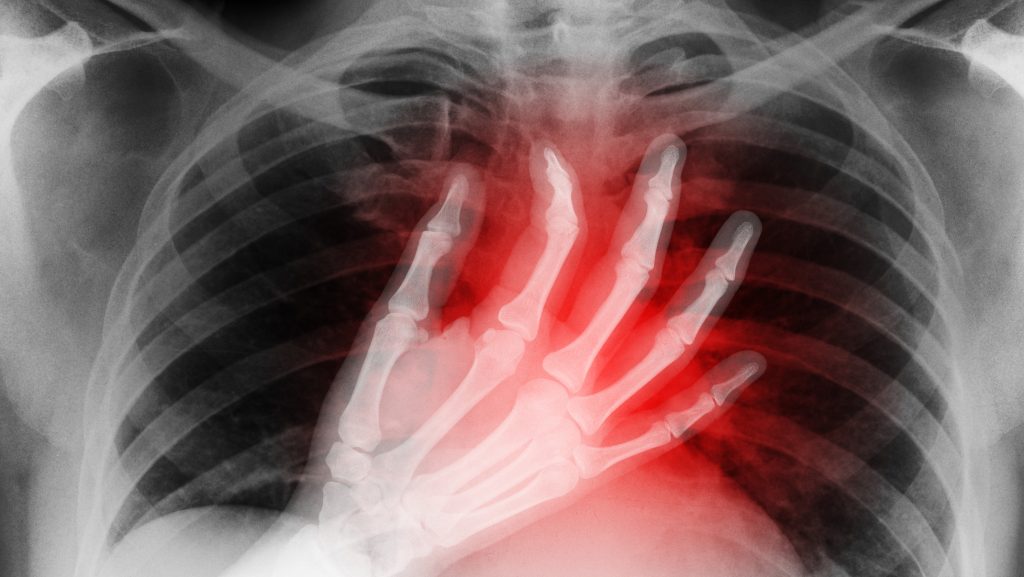

Elképesztő eredményről számoltak be az amerikai Northwestern Egyetem kutatói: állításuk szerint kifejlesztettek egy olyan, mesterséges tüdőrendszert, amely két napon át képes volt helyettesíteni egy beteg súlyosan károsodott tüdejét. Ez az idő elég volt ahhoz, hogy felkészítsék a férfit egy kettős tüdőátültetésre, és sikerült megmenteni az életét, írja a Gizmodo.

Az egyetlen remény a gyógyulásra egy kettős tüdőátültetés volt, az orvosai szerint azonban a férfi szervezete túl gyenge volt egy ilyen beavatkozáshoz. A tüdők megőrzése ugyanakkor veszélyeztette volna az átültetett szervek túlélési esélyeit. Az orvosok végül úgy döntöttek, hogy teljes egészében eltávolítják a férfi tüdejét, és egy ideiglenes rendszert hoznak létre, ami stabilizálja az állapotát, míg a transzplantációnak nem lesz orvosi akadálya.

A légzőszerveket kiváltó rendszer (TAL) úgy lett kialakítva, hogy teljes mértékben átvegye a tüdő funkcióit. Még a férfi folyamatos szepszise ellenére is stabilan tudta tartani a szívműködést.